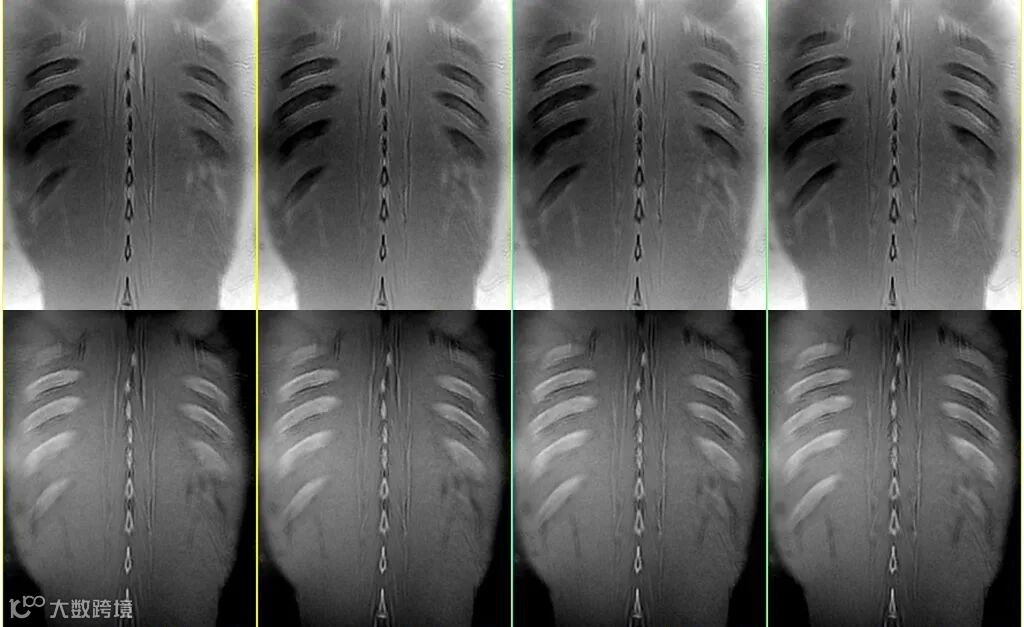

上图△,肋骨成像。成像FA =2°,体素1.0*1.0*1.0mm。

翻转角FA:FA越大,信噪比越高,但随着FA的增加骨质与周围软组织对比度会变差,如下图▽。